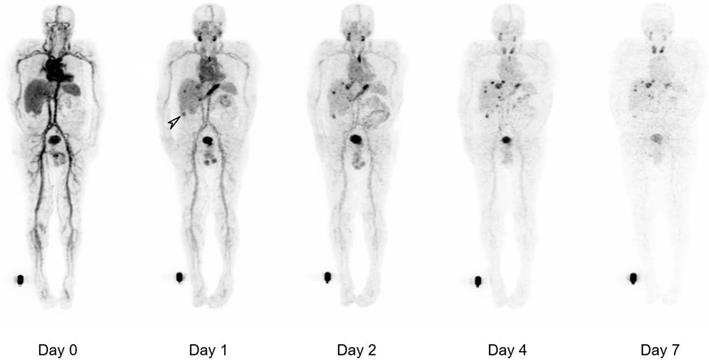

Figure 3

Whole body biodistribution of 124I-PEG-AVP0458 in Patient 3 (1 mg/m2 dose level). Sequential whole-body PET images acquired over one week following a single 124I-PEG-AVP0458 infusion showing gradual blood-pool clearance and no specific normal tissue uptake. Localisation of the diabody to sites of metastatic prostate cancer are evident from day 1 and an incidental TAG-72 positive colon tumor was also identified (arrow). Late visualization of the thyroid is likely to reflect free 124I due to late de-iodination of the agent.

The biodistribution of 124I-PEG-AVP0458 was assessable in 5 of 6 patients, as patient 2 (1 mg/m2 cohort) dose of 124I-PEG-AVP0458 was extravasated and rendering the patient data not evaluable for biodistribution or dosimetry analysis. Figure 2 includes qualitative tumor uptake results for individual patients. Whole body images and representative biodistribution pattern are presented in Figure 3 (1 mg/m2 dose level) and selected transaxial PET/CT sections to highlight metastatic prostate cancer tumor regions are presented in Figure 4 (10 mg/m2 dose level).

124I-PEG-AVP0458 PET imaging showed stable and consistent biodistribution across all patients at both dose levels, with gradual clearance from blood with time, and no significant normal tissue uptake. In particular, no discernible kidney uptake of 124I-PEG-AVP0458 was observed. Tumor uptake was rapid and evident by 1‑2 days post-injection, with sites of metastatic disease in lymph nodes and liver identified. Image-derived time-activity data were used to calculate the median time-integrated activity coefficients (residence time) of 124I-PEG-AVP0458 in all organs and tissues (Table S2). The organ receiving the highest mean absorbed dose was the thyroid gland (2.21 ± 0.61 mGy/MBq). Maximal tumor uptake observed was 12.2 × 10-3 %ID/mL at 7 days. The specific tumor absorbed dose ranged from 1.25 mGy/MBq to 4.75 mGy/MBq (mean ± SD = 2.87 ± 1.49 mGy/MBq), and the measured absorbed tumor dose ranged from 235.88 mGy to 833.06 mGy (mean ± SD = 605.32 + 322.83 mGy).

Whole body clearance of 124I-PEG-AVP0458 was consistent among patients, and across dose levels (Figure 5). There were no statistically significant differences between the two dose levels. The mean effective half-life of 124I-PEG-AVP0458 (measuring the time for decrease of 124I-PEG-AVP0458 to half the initial value by both biological clearance and radioactive decay) was 56.74 ± 8.80 hours in the 1 mg/m2 dose group, and 57.84 ± 2.31 hours in the 10 mg/m2 dose group (P=0.97). The mean biological half-life of 124I-PEG-AVP0458 (measuring only the biological clearance of 124I-PEG-AVP0458) was 136.61 ± 21.62 hr in the 1 mg/m2 dose group, and 137.24 ± 12.89 hr in the 10 mg/m2 dose group (P =0.89). The effective whole body dose was calculated at 0.56 ± 0.09 mSv/MBq.